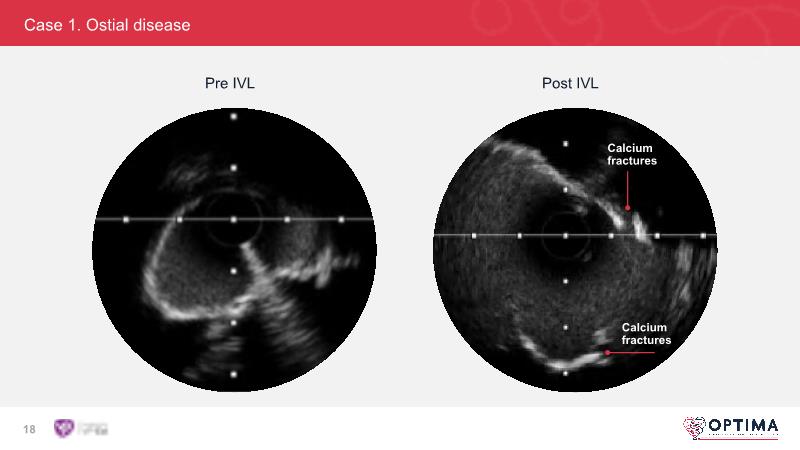

Cracking calcium: intravascular lithotripsy’s unique mode of action in treating calcified lesions – What's the evidence?

Watch this GulfPCR-GIM 2022 session to understand the unique mechanism of action of IVL, the use of intravascular imaging in calcium identification, the gender gap, disrupted CAD trials, and the evolution of treatment of calcified lesions together with the role of IVL.

- To be familiar with intravascular lithotripsy and its unique mechanism of action and the use of intravascular imaging in identifying calcium